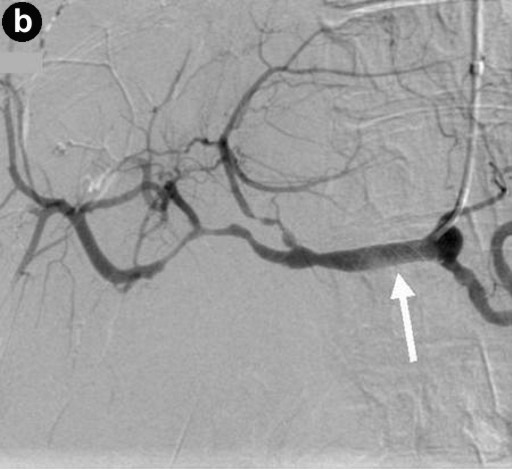

The sites of haemorrhage, management and outcome are summarised in Table 1. All PPH were classified by us as ISGPS type C. The initial CT angiogram revealed the source of the bleeding in all patients and 6 patients went on immediately to have mesenteric angiography. Stent grafting (n=2) was used to control bleeding sites in the common hepatic artery (Figure 1) and coil embolisation (n=5) was employed for bleeding sites arising from branches of superior mesenteric artery, gastroduodenal artery and splenic artery (Figure 2). One patient who underwent metal coil embolisation of proximal hepatic artery for a large psuedoaneurysm from the stump of gastroduodenal artery required further coil packing of the vessel and a follow-up CT scan two weeks after the initial embolisation demonstrated persistent flow in the common hepatic artery. No laparotomy was ever needed after embolization.

Figure 1. Digitally subtracted angiographic images. a. A pseudoaneurysm arising from the stump of the gastroduodenal artery (arrowed). The tip of the catheter is in the common hepatic artery. b. Image from the same patient after deployment of a 6x20 mm stent-graft (arrowed) in the common hepatic artery across the origin of the gastroduodenal artery. The stent-graft has excluded flow from the gastroduodenal stump. The tip of the catheter is in the common hepatic artery. |